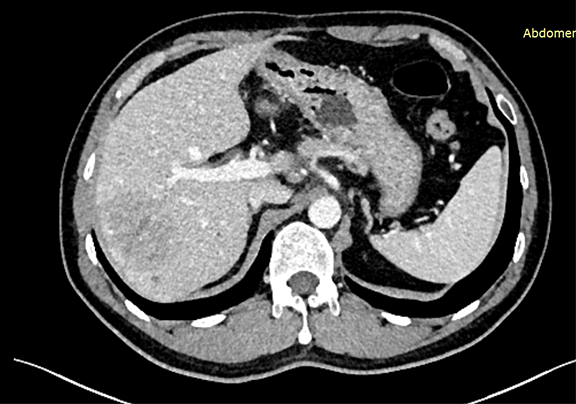

下腹部增强CT示:符合肝脏术后改变,请结合临床;肝右叶占位性病变,考虑肝Ca 可能性大。

将0.625mm双源薄层CT资料的静脉期和动脉期Dicom格式文件导入海信CAS系统。

通过调节窗宽窗位调整CT序号,对肿瘤,肝实质,胆囊,下腔静脉,肿瘤,肝动脉、门静脉及肝静脉等进行三维重建;系统自动计算肿瘤体积和肝脏体积。

模拟手术操作,自动计算切除肿瘤体积。肝脏体积为1427ml,肿瘤体积为65.97ml,肿瘤体积为肝脏体积的4.6%,通过比对40-50岁正常肝脏体积为1368.38±279.24ml,通过术前模拟手术,精准判断切除后剩余肝脏体积能耐受,避免肝衰竭发生。

术前CT检查:

动脉期

静脉期